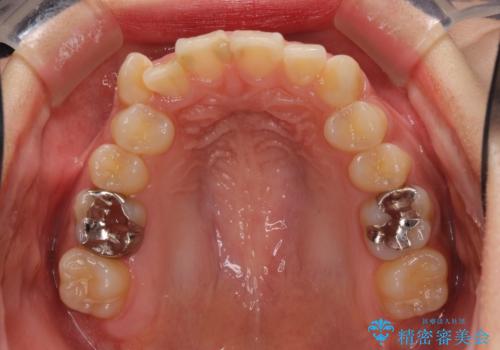

- 上下の八重歯を気にして来院された患者様です。

上下ともに八重歯の後ろの歯を1歯ずつ抜歯し、補助装置(リンガルアーチ)を用いて八重歯の位置を改善し、その後インビザラインにより矯正治療を行うこととしました。

途中海外留学をされたため、治療期間は長くなりましたが、事前に補助装置やワイヤー装置を併用したことで、きれいな歯列に仕上げることができました。